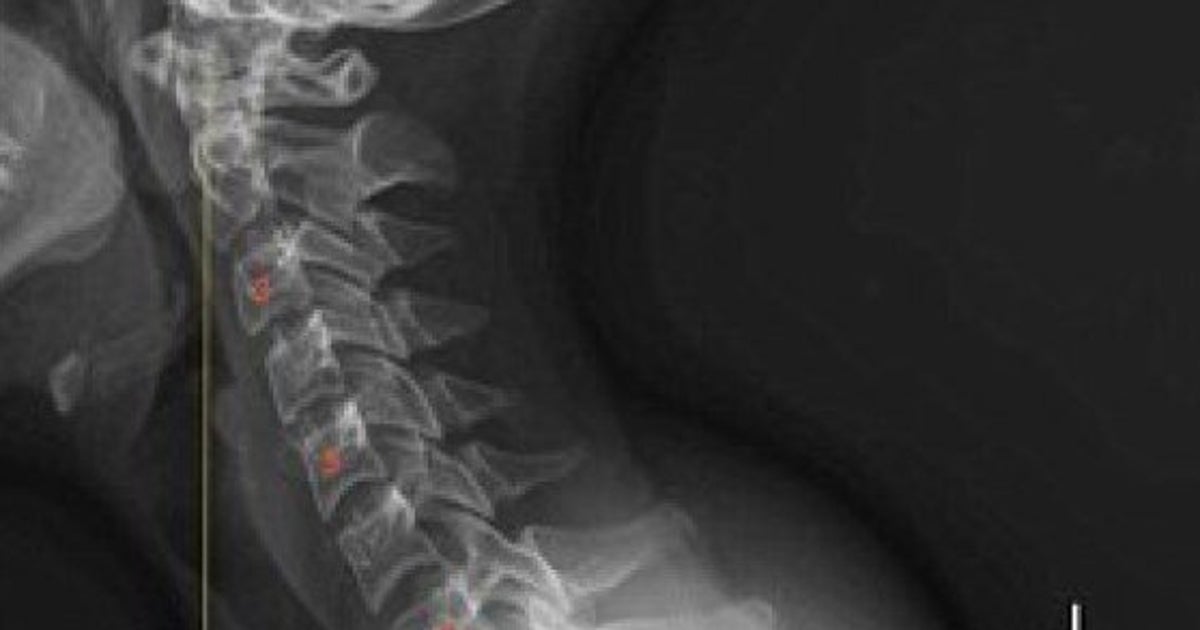

La Lastra Che Mostra I Danni Da Smartphone Alla Spina Dorsale Di Un Bambino Di Sette Anni Foto L Huffpost

La Lastra Shock Del Collo Di Un Bimbo Di 7 Anni Colpa Dello Smartphone

Supporti per schiena, collo e spalle Benvenuto nella sezione "Supporti per schiena, collo e spalle" della categoria Salute e cura della persona di Amazonit scopri la nostra selezione in Supporti lombari, Supporti per spalle, Busti ortopedici, Collo e tanto altro. Come si legge una lastra alla schiena?. La lastra che mostra i danni da smartphone alla spina dorsale di un bambino di sette anni (FOTO) causando spesso problemi alla testa, al collo, alle spalle e alla schiena".